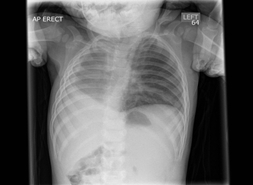

A 9 months old infant presented with recurrent lower respiratory tract infections and wheezy episodes. On examination, he had respiratory distress and wheeze, which parents reported to be present for last 3 months. Chest X-ray showed a large right sided homogeneous opacity and shift of the mediastinum to right side (Figure 1). CT thorax showed right pulmonary hypoplasia, with only partial formation of the right upper lobe. The hypoplastic lung was supplied by a small calibre right main pulmonary artery. The azygos vein coursed horizontally into the superior vena cava, suggesting that part of the formed lung was azygos lobe. (Figure 2) There were also segmental anomalies of C7 and T1 vertebra leading to scoliosis of cervical spine. Echocardiogram was normal. He was discharged under respiratory team follow up and has been referred to orthopaedic clinic for scoliosis.

Figure 1: Chest X-ray showing a large right sided homogeneous opacity and shift of the mediastinum to right side